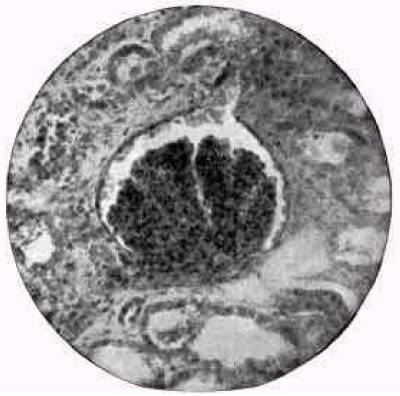

Figure 32. A glomerulus.

Acute exudative nephritis. (Delafield).

This image is from Acute Bright's Disease. in Thomas' Eclectic Practice of Medicine.